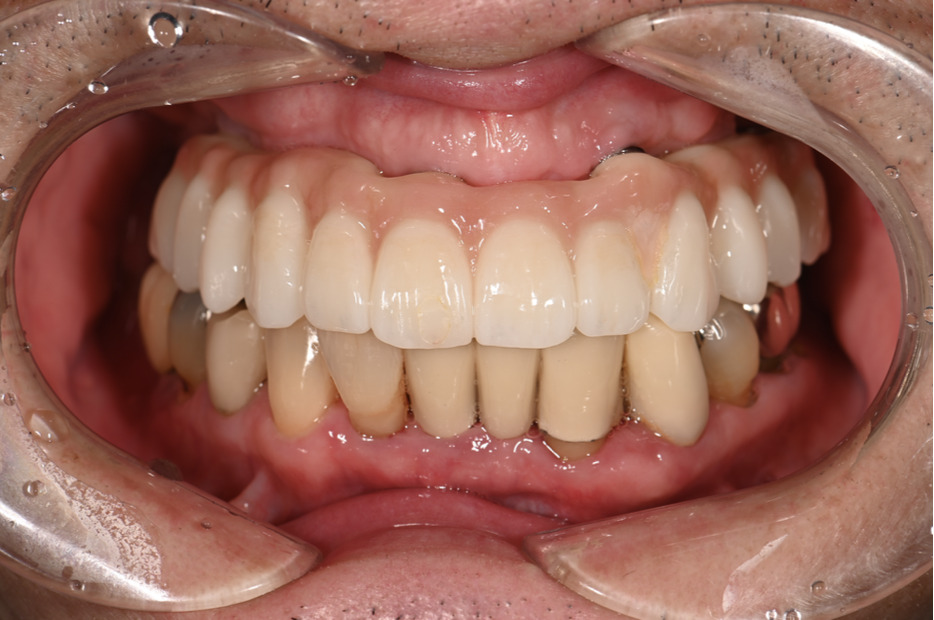

| 主訴 | 歯がグラグラして噛めない |

|---|---|

| 治療内容 | 上顎、下顎に対するインプラント治療 |

| 治療期間 | 1日 |

| 治療費 | 409万2千円 |

| 治療 リスク | 最終的な歯が入るまでは仮歯になります。 |